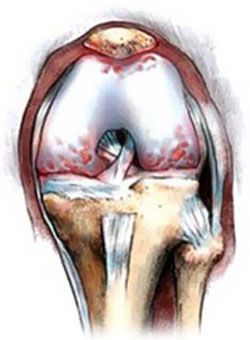

Atunci când factorii negativi ai cartilajului devine dur, mult mai subțire, iar în unele cazuri chiar și un uscat și acoperit cu fisuri. alunecare moale este imposibil, în schimb, există o frecare puternică, suprafața articulațiilor începe să se agațe unul de altul. procesul de degenerare Netratată continuă. În cazul în care oasele de amortizare reduse incepe sa se uniformizeze, crescând astfel zona de îmbinare. Pacientul poate observa apariția de osteofite - excrescente osoase, având forma de noduli.

Din cauza lipsei de sângerare și mobilitatea unei structuri comune de genunchi incepe sa se atrofieze, lichidul articular devine gros, vâscos. Acest lucru duce la o slăbire a chitanței de nutrienți minerali de cartilaj, care afecteaza foarte mult starea pacientului.

Din cauza subțierea cartilajului reduce semnificativ distanta dintre oasele articulate. Când începe mersul pe jos articulatii puternice frecare. procese distructive continuă să progreseze mai mult și mai mult. Pacientul incepe sa se simta rigiditate dimineata, conditie dureroasa. Acest lucru se întâmplă atunci când sarcina, și în pace totală. Simptomele dureroase sunt deosebit de pronunțate de mers pe jos în sus pe scări. Pentru a preveni piciorul dureros, persoana începe să șchiopăteze. În cazurile severe, pacientul nu poate merge fără baston sau cârje.

Când se execută gradul de cartilaj osteoartrita este aproape complet distrus. Restaurare cartilajului nu ajută la nici un unguente și medicamente, doar o intervenție chirurgicală poate ajuta în acest caz.

În artroză, cartilajul devine mai subtire de tesut conjunctiv articulare, oasele, prin urmare, dăunătoare